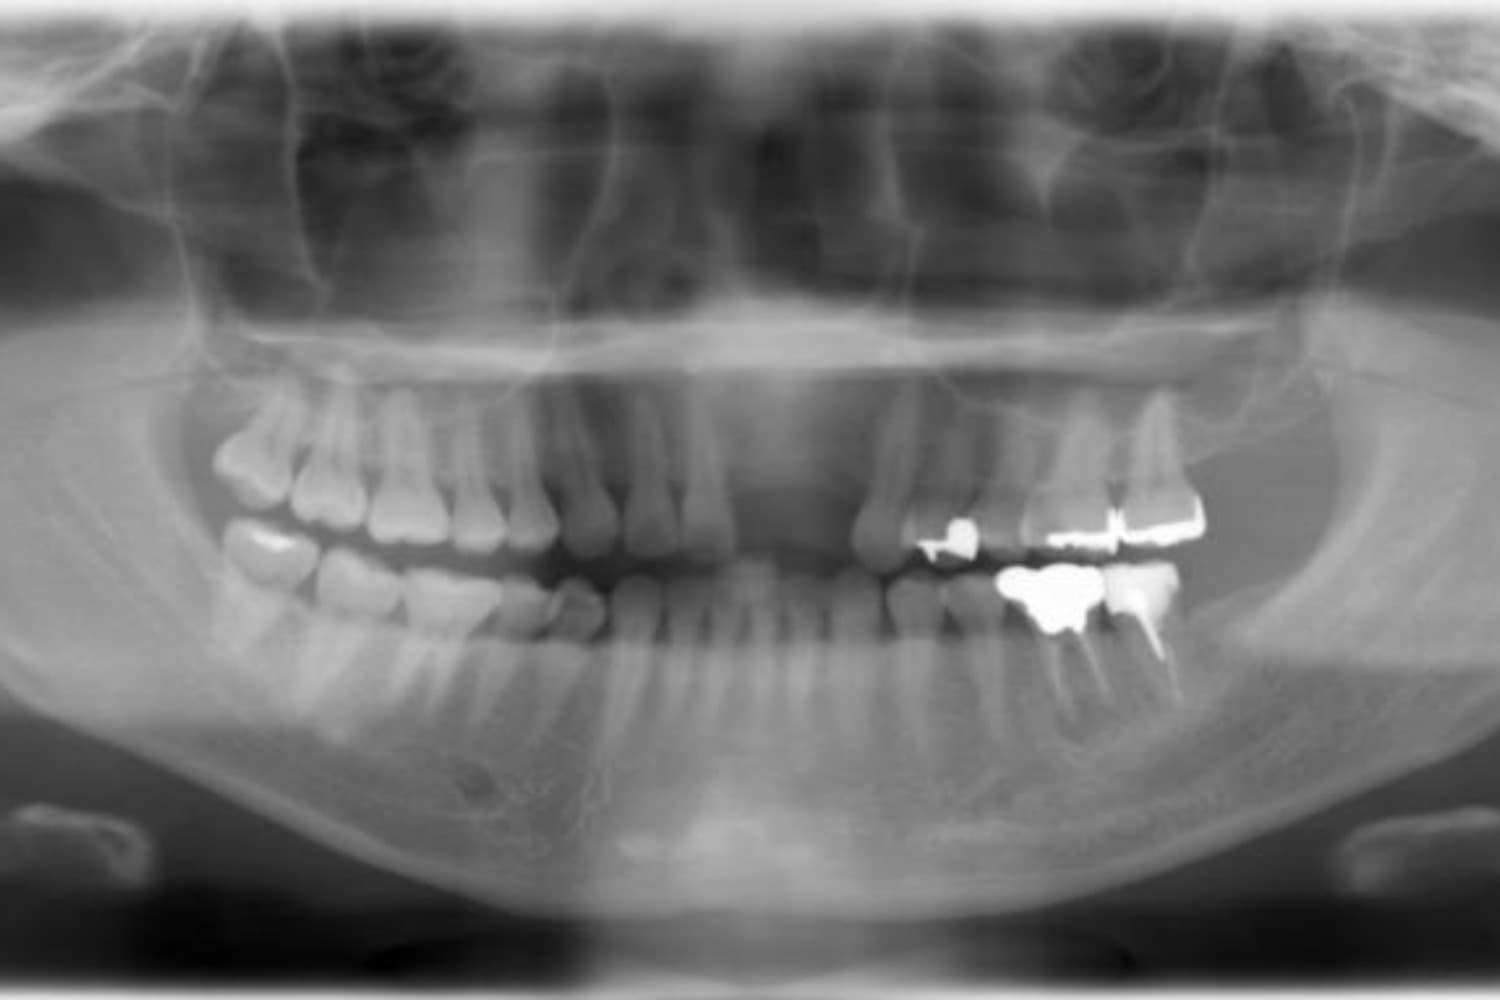

下顎大臼歯3本欠損症例

Before

左下第一大臼歯は保存が困難な状態であったため抜歯をおこないました。あわせて、ご来院時から欠損していた右下第一・第二大臼歯も含め、欠損部の補綴方法についてご説明し、インプラント治療を選択されました。

年齢

60歳

性別

男性

主訴

左下の第一大臼歯は別の医院で治療中でしたが、治療が思うように進まず、加えて他の箇所にも痛みが続いたことから、当院にご相談いただきました。

治療期間

10ヵ月

費用

140万円

副作用・リスク

インプラント治療は外科的な処置を伴い、多少の腫れや痛みが出ることがあります。 多くの場合は鎮痛薬で和らげることができます。